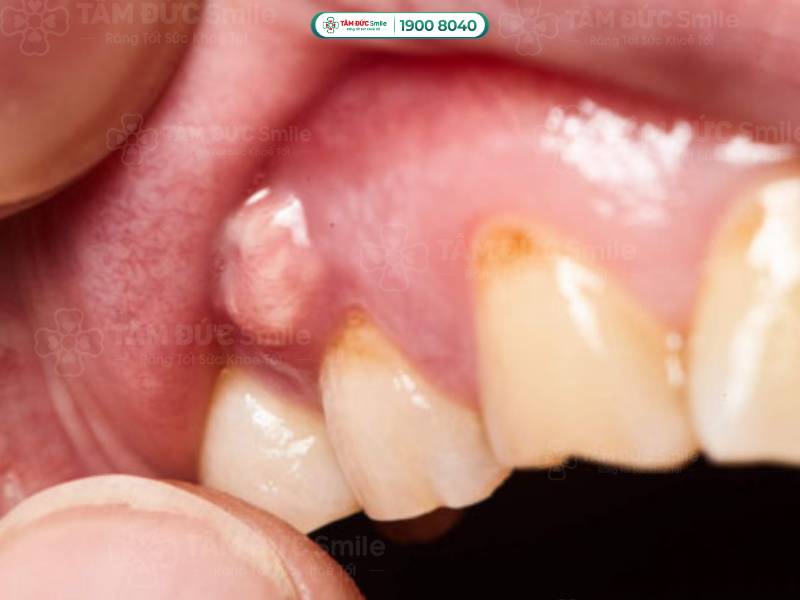

1.1.2. Áp xe chóp răng (áp xe chân răng)

Áp xe được hiểu là tập hợp mủ được hình thành từ các tế bào bạch cầu chết, vi khuẩn và những mảnh mô vụn. Vấn đề áp xe chóp răng bắt đầu từ tủy răng và kết thúc ở phần chóp chân răng.

Vấn đề áp xe chóp răng bắt đầu từ tủy răng và kết thúc ở phần chóp chân răng

Chứng áp xe chóp răng thường khó nhận biết bằng mắt thường. Người bệnh có những biểu hiện dưới đây nên đến thăm khám ở các cơ sở y tế để được chẩn trị chính xác:

- Đau nhức răng, người bệnh chỉ cần nhai nhẹ cũng có cảm giác đau.

- Ê buốt răng khi sử dụng các loại thực phẩm nóng, lạnh.

- Vùng áp xe có thể làm hành sốt, nổi hạch ở cổ, khiến người bị mệt mỏi.

- Phần lợi dưới chân răng bị sưng; khi soi gương, bạn có thể thấy hạt mủ tụ ở phần chân răng gây đau.